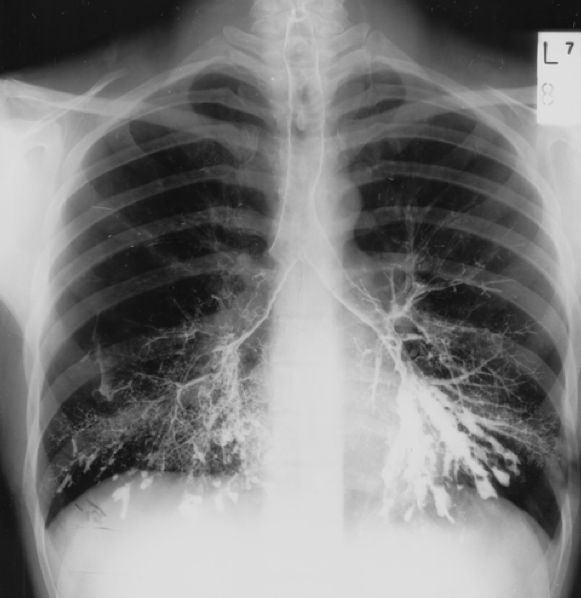

Bilateral hilar lymphadenopathy consistent with sarcoidosis